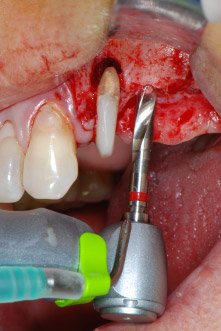

Преди поставянето на импланта, инфектираната тъкан е отстранена от алвеоларната кост в имплантното ложе и около зъба-абатмънт с накрайник, проектиран за оформяне на костта и събиране на костни блокове (Piezomed, накрайник B5) (Фиг. 6 и 7).

Имплантологичното ложе е подготвено в позиции 25 и 26 с ротиращи инструменти, използвайки обратен наконечник 20:1 с усъвършенстван и мощен имплантологичен мотор (Implantmed, W&H) (Фиг. 8).